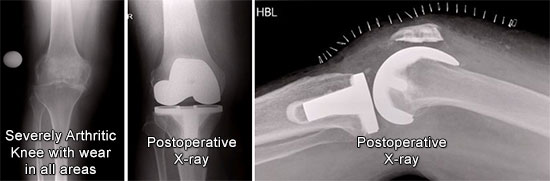

Pain After Knee Replacement - About.com Health

Persistent pain after knee replacement is the most common complication after this surgery. A knee replacement is done when the knee joint has worn out, X-rays and other studies can assess alignment and loosening. ... Read Article